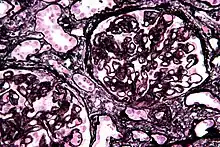

| Micrograph of membranous nephropathy showing prominent glomerular basement membrane spikes. Jones' stain. | |

- By light microscopy, the basement membrane is observed to be diffusely thickened. Using Jones' stain, the GBM appears to have a "spiked" or "holey" appearance.